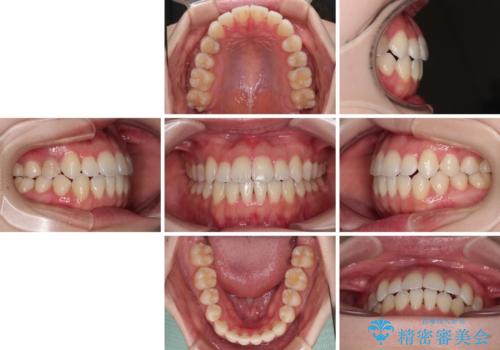

舌突出癖による開咬 舌のトレーニングを行いながら前歯の隙間を改善

- 上下前歯の隙間を気にして来院された患者様です。

前歯が、舌の突出癖により上下前歯が非接触となっている状態でした。

上下前歯が非接触である開咬は、インビザラインによる治療がお勧めではありますが、しっかりと使う自信がないとのことで、ワイヤー装置にて治療を行うこととしました。

ワイヤー矯正での開咬改善には時間がかかります。

舌の突出癖改善のトレーニングをしっかりと行っていただき、上下前歯が接触する咬み合わせを達成することができました。